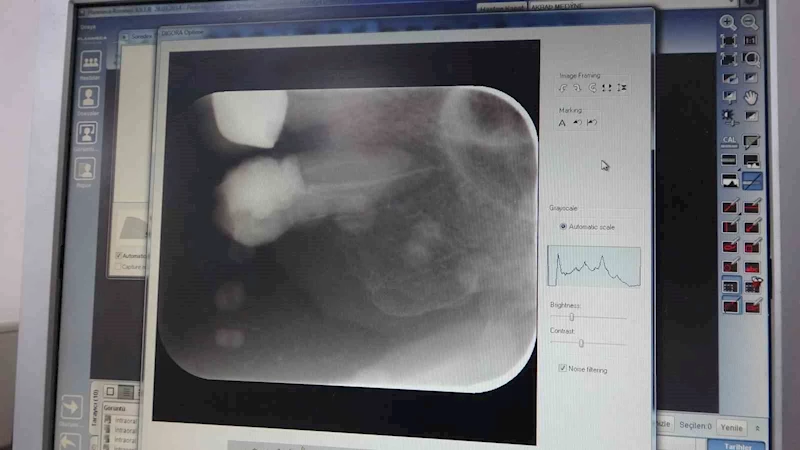

İnönü Üniversitesi Diş Hekimliği Fakültesi Dekanı ve Endodonti Uzmanı Prof. Dr. Neslihan Şimşek, Diş Hekimliği Fakültesi’ne geçtiğimiz yıl 303 bin hastanın başvuru bulunduğunu belirterek yaklaşık 11 bin hastaya ise kanal tedavisi uygulandığını kaydetti.

2024 yılında 303 bin hastanın başvuru yaptığını vurgulayan Şimşek, "2024 yılında 303 bin hasta başvuru yaparken, bunlardan yaklaşık 11 bin hastaya kanal tedavisi uygulandı" ifadelerini kullandı. Şimşek, fakültede toplamda 12 milyon 250 binin üzerinde diş tedavisi gerçekleştirildiğini de söyledi.